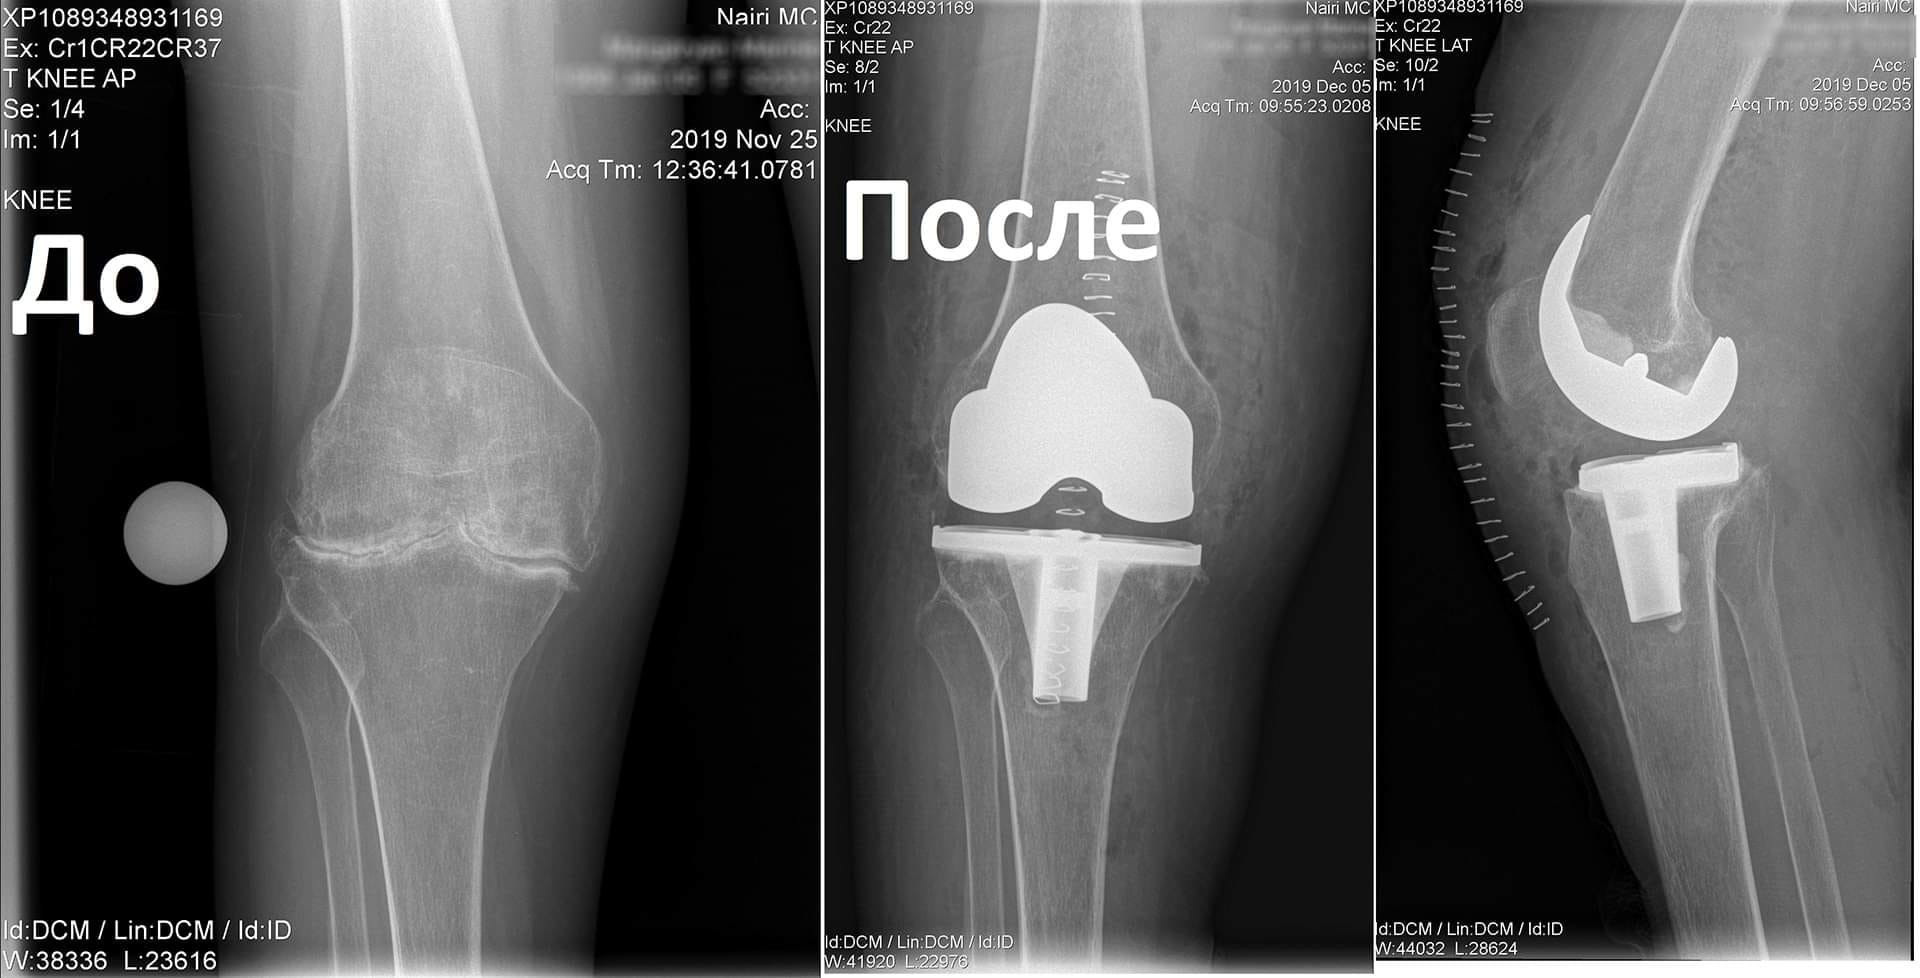

Կլինիկական դեպք. երկկողմանի գոնարթրոզ՝ ծնկահոդերի արթրոզ

Պացիենտը դիմել էր «Նաիրի» բժշկական կենտրոն` նստասալյակի օգնությամբ, ծանրագույն ցավերով, շարժումների խիստ սահմանափակումով:

Ծանրագույն պոլիարթրիտի հետևանքով առաջացել էր ծնկահոդերի արթրոզ։

Նման դեպքերում վիրահատույթունից առաջ պահանջվում է լրջագույն նախապատրաստում և հետվիրահատական հսկողություն:

Նախավիրահատական ընթացակարգից հետո իրականացվել է զույգ ծնկահոդերի փուլային էնդոպրոթեզավորում: Վիրահատությունից մի քանի ամիս անց պացիենտը չի ունեցել ցավեր, ազատ քայլել է և սկսել է ապրել լիարժեք կյանքով: